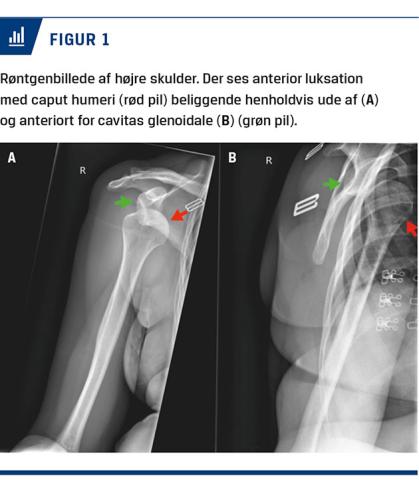

En røntgenundersøgelse af højre skulder viste højresidig FSL uden komplicerende fraktur (Figur 1).